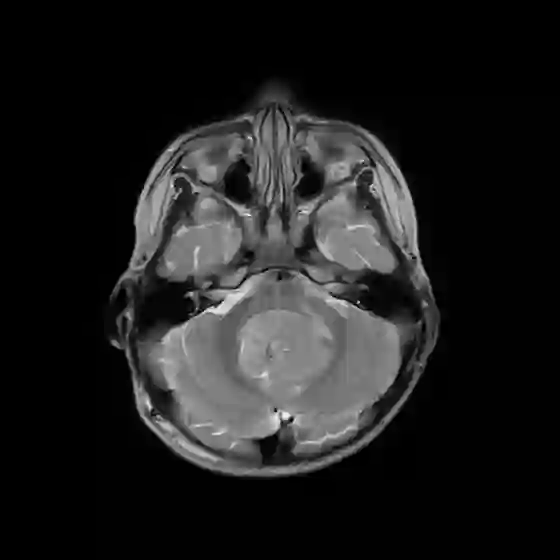

The field of explainability in artificial intelligence has witnessed a growing number of studies and increasing scholarly interest. However, the lack of human-friendly and individual interpretations in explaining the outcomes of machine learning algorithms has significantly hindered the acceptance of these methods by clinicians in their research and clinical practice. To address this, our study employs counterfactual explanations to explore "what if?" scenarios in medical research, aiming to expand our understanding beyond existing boundaries on magnetic resonance imaging (MRI) features for diagnosing pediatric posterior fossa brain tumors. In our case study, the proposed concept provides a novel way to examine alternative decision-making scenarios that offer personalized and context-specific insights, enabling the validation of predictions and clarification of variations under diverse circumstances. Additionally, we explore the potential use of counterfactuals for data augmentation and evaluate their feasibility as an alternative approach in our medical research case. The results demonstrate the promising potential of using counterfactual explanations to enhance trust and acceptance of AI-driven methods in clinical research.